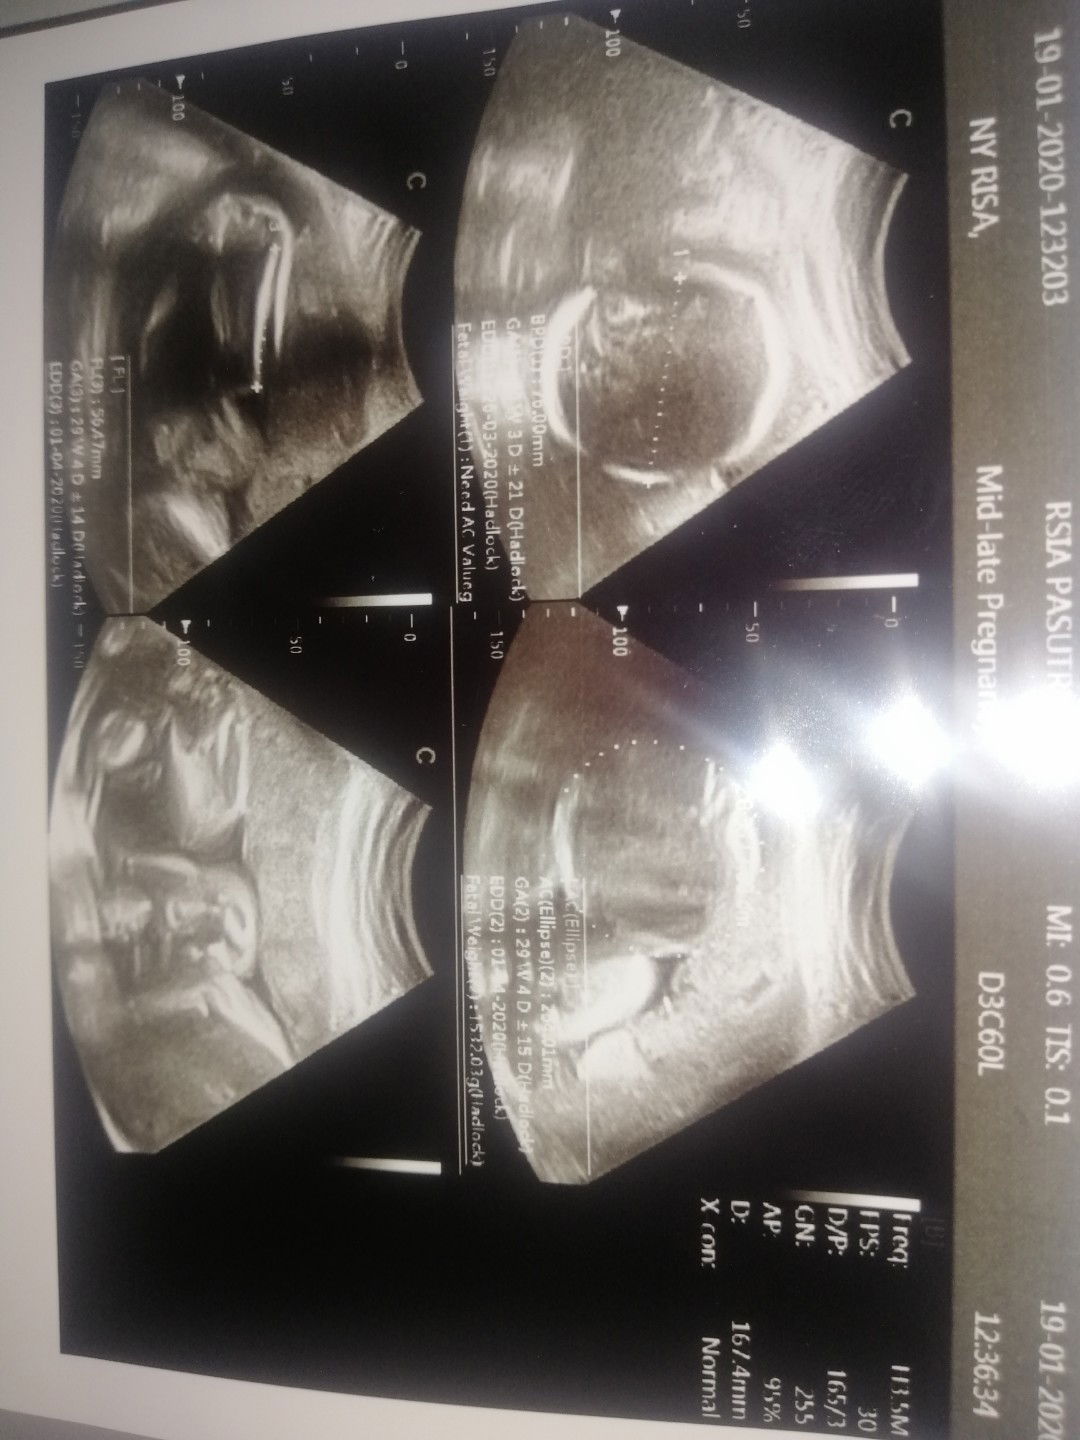

Hasil usg

Bun maaf tanya dong , tadi saya habis usg lupa tanya tinggi/ panjang bayi. Yg saya tanya berat sama tingginya gimana normal ? Dan dokternya bilng normal ko. Tapi detail tingginya saya gk tau berapa ..yg tau cara bacanya tolong di bantu yah bun ..trimaksih ??

Tb janin gabisa diukur lewat usg bun, posisi dia di rahim kan meringkuk..nanti pas lahir baru ketauan